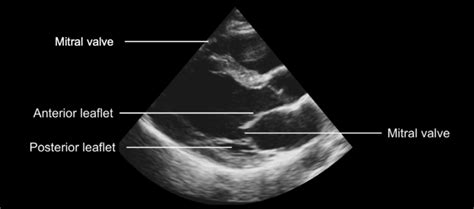

The Role of Echocardiography in Detection

Guys, let’s talk about the unsung hero in detecting that hockey stick mitral valve echo : echocardiography . This imaging technique is absolutely critical, and honestly, it’s the gold standard for visualizing this specific abnormality. Echocardiography, or ‘echo’ as we commonly call it, uses high-frequency sound waves to create real-time images of your heart. Think of it like sonar for your heart! A technician, usually called a sonographer, places a transducer (a wand-like device) on your chest, and these sound waves bounce off the different structures of your heart – the chambers, the walls, and of course, the valves. The echoes are then processed by a computer to build detailed pictures and even moving images of your heart in action. For detecting the hockey stick mitral valve echo , echocardiography is invaluable because it allows us to see the dynamic motion of the mitral valve leaflets throughout the cardiac cycle. We’re not just looking at a static picture; we’re watching how the anterior mitral valve leaflet moves as the heart beats. In a healthy heart, this leaflet opens widely and gracefully during diastole to allow blood flow. However, in conditions like hypertrophic cardiomyopathy (HCM), the thickened septum pushes into the ventricular cavity. The echocardiogram clearly shows how this abnormal anatomy affects the leaflet’s movement. We can visually track the anterior leaflet being drawn towards the thickened septum, creating that characteristic elongated, curved, ‘hockey stick’ shape. Different views within the echocardiogram, like the parasternal long-axis view, are particularly useful for observing this phenomenon. Doppler ultrasound, another component of echocardiography, can also assess blood flow patterns. It can help quantify the degree of left ventricular outflow tract (LVOT) obstruction that often accompanies the hockey stick mitral valve appearance. This helps the doctor understand the severity of the condition and its impact on blood flow. The diagnostic power of echo is immense. It can differentiate between various causes of heart conditions, assess the extent of muscle thickening, measure chamber sizes, and evaluate overall heart function. When it comes to the hockey stick mitral valve echo , it’s a very specific sign that guides the clinician towards a diagnosis of HCM or similar obstructive conditions. Without echocardiography, identifying this subtle yet significant dynamic abnormality would be incredibly difficult, if not impossible. It’s a non-invasive, readily available, and highly informative tool that provides a window into the intricate mechanics of the heart, allowing for precise diagnosis and effective management planning. So, next time you hear about an echo, remember it’s a sophisticated piece of technology doing some truly amazing work, especially when it comes to spotting signs like the hockey stick mitral valve.